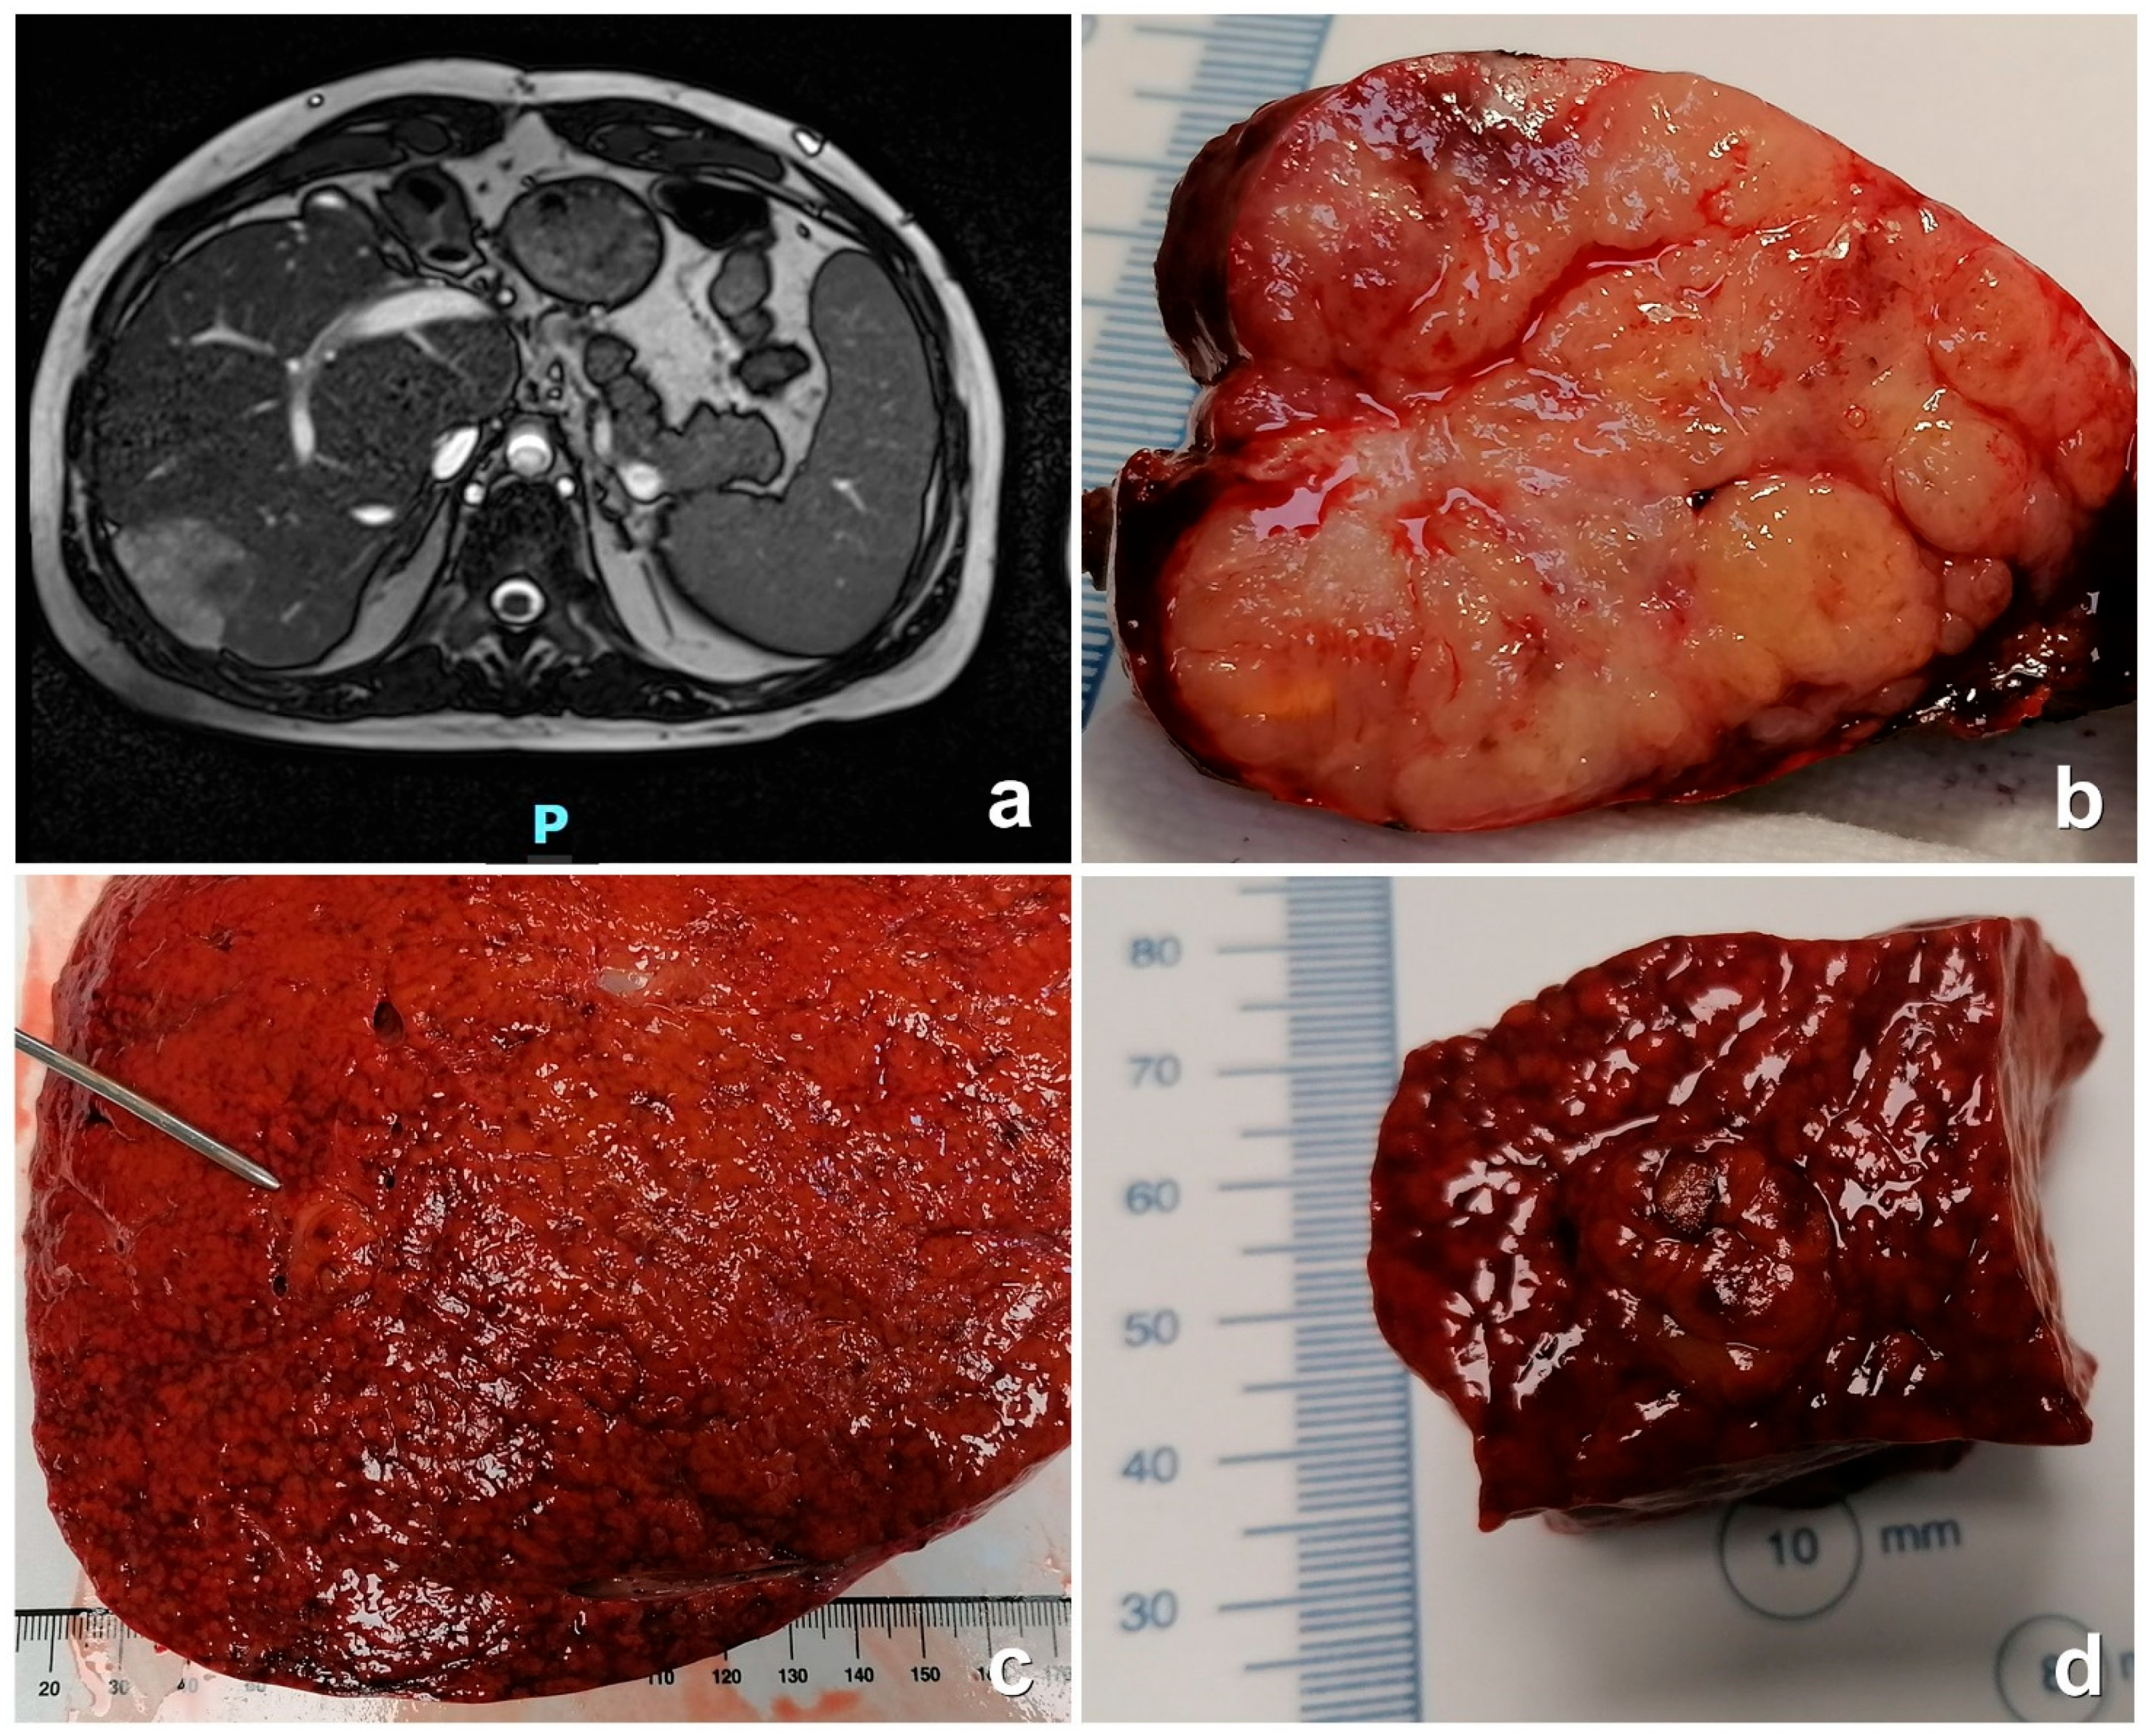

| Patient | M/F | Age at FP (y) | CHD | Age at Diagnosis (y) | Interval Fontan-FALD (y) | GGT n.v. 11–65 | Platelet n.v. 150–450 | Serum AFP n.v. < 8.10 | Tumor Size | Prognosis/Death |

|---|---|---|---|---|---|---|---|---|---|---|

| P1 | F | 4 | Complete AVSD—RV dominant | 20 | 16 | 100 | 208 × 103/uL | 2.43 ng/mL | 4.5 cm | Alive HTx 2019 |

| P2 | F | 3 | TA-PA | 22 | 22 | 99 | 175 × 103/uL | 11,458.00 ng/mL | 4.5 cm | † (6 m post-FALD) |

| P3 | M | 2 | DILV and TGA | 18 22 | 16 * 20 ** | 37 | 173 × 103/uL | ** 447.8 ng/mL | 8 cm | Alive HTx 2014 |

| P4 | F | 6 | TA-PSt-TGA | 34 | 28 | 154 | 182 × 103/uL | 3005.00 ng/mL | 3 cm | † (1 y post-FALD) |

| P5 | M | 8 | PA with intact IS | 32 | 16 | 94 | 111 × 103/uL | 9.43 ng/mL | 2.3 cm | Alive |

| US | MDCT | MRI | |||||

|---|---|---|---|---|---|---|---|

| Arterial Phase | Portal Phase | Late Phase | Arterial Phase | Portal Phase | Late Phase | ||

| P1 FLCA | Iso-echoic | Slightly hyper-dense Wash-in | Hypo-dense Wash-out | Slightly hypo-dense with hyperdense ring | Hyper-intense Wash-in | Hypo-intense Wash-out | Hypo-intense |

| P2 HCC | Hypo-echoic | Hyper-dense Wash-in | Hypo-dense Wash-out | Hypo-dense | Hyper-intense Wash-in | Hypo-intense Wash-out | Hypo-intense |

| P3 ICC | Hypo-echoic | Hypo-dense No wash-in | Hyper-dense | Hypo-dense | ND | ND | ND |

| P4 HCC | Iso-echoic | Slightly hyper-dense Wash-in | Hypo-dense Wash-out | Slightly hypo-dense with hyperdense ring | ND | ND | ND |

| P5 HA | Hyper-echoic | Slightly hyper-dense No wash-in | Hyper-dense | Hypo-dense Wash-out | Iso-intense | Hyper-intense | Hypo-intense |